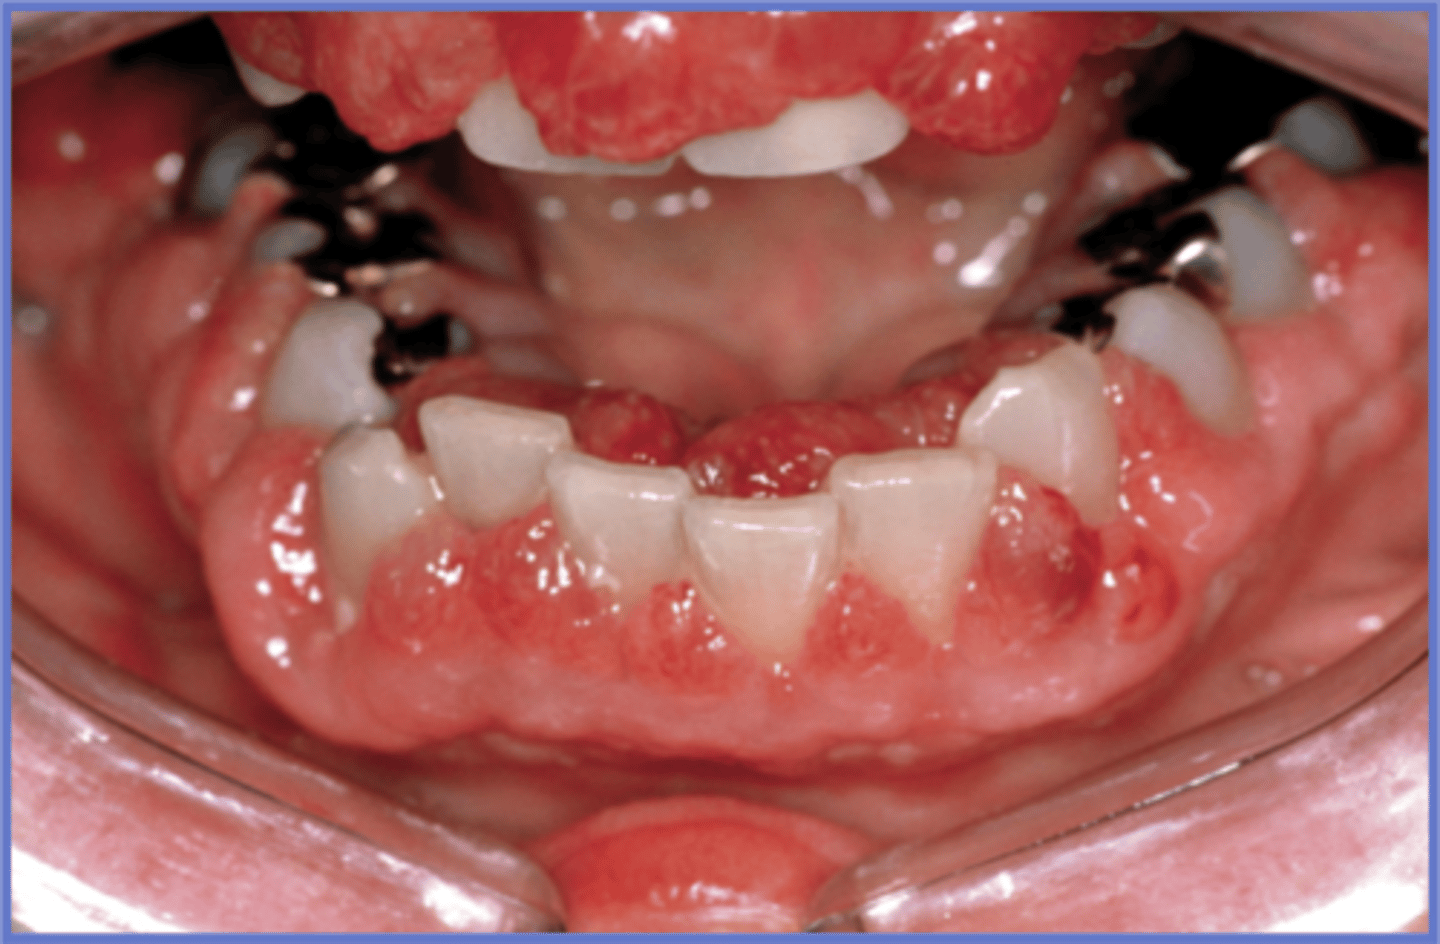

What is inflammatory papillary hyperplasia? (+ other name, common location)

AKA denture papillomatosis

⢠red (or pink) cobblestone appearance of hard palate

⢠under a prosthesis